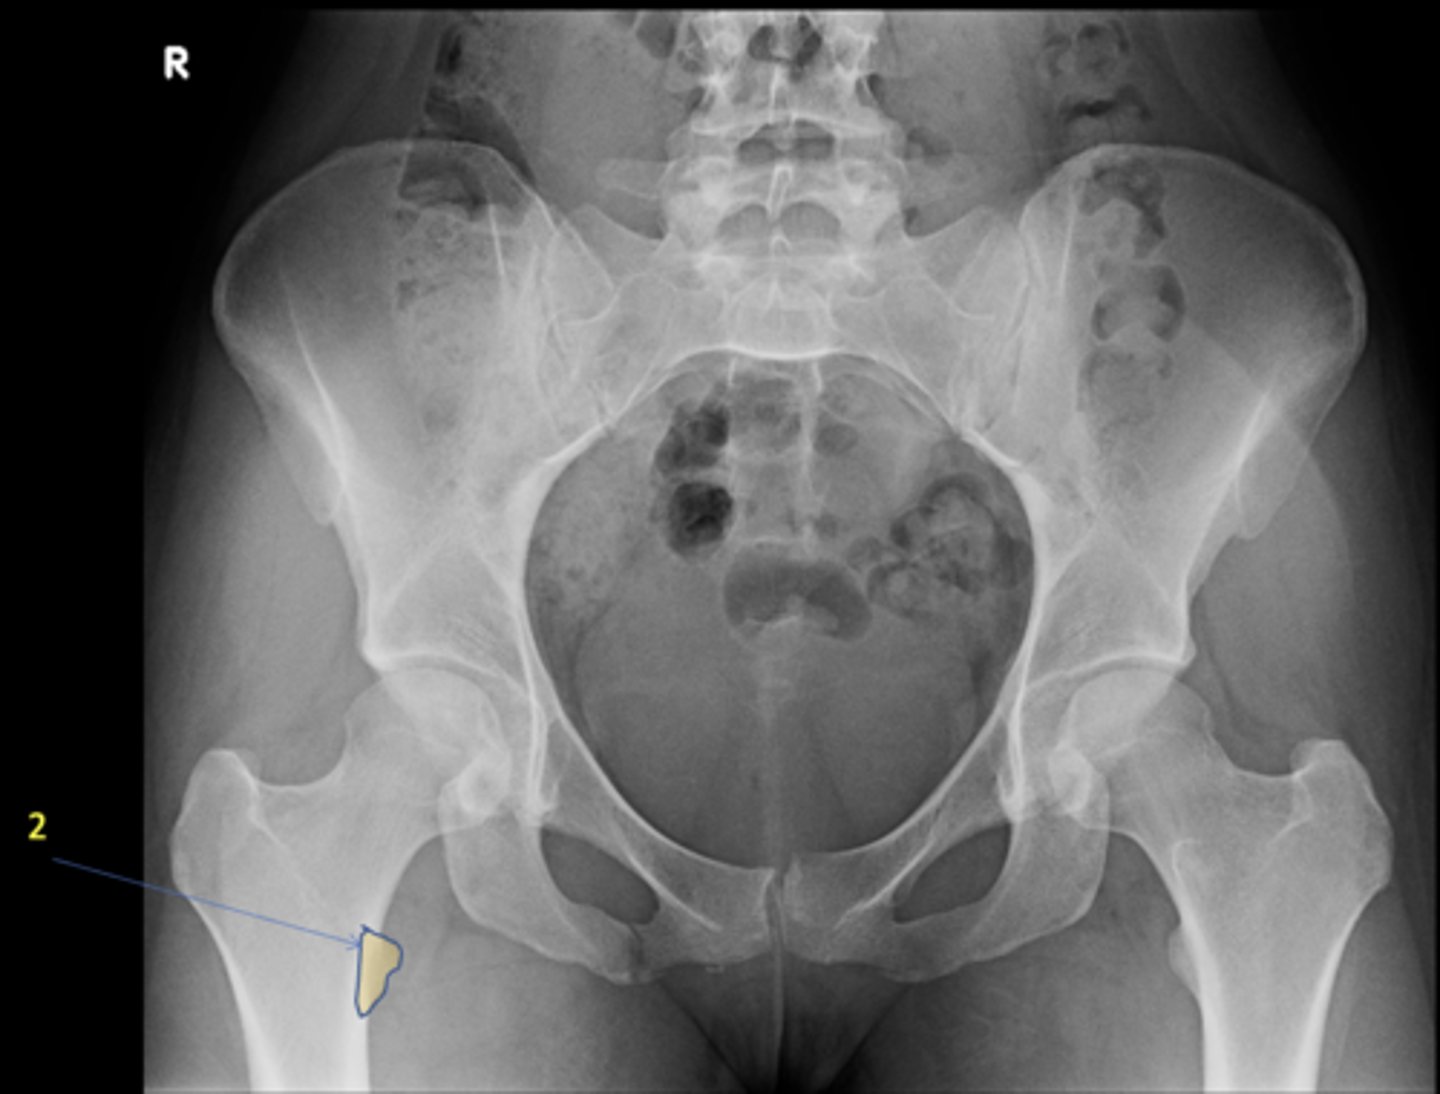

1

New cards

AP pelvis

2

Right lesser trochanter

ID 2

<p>ID 2</p>